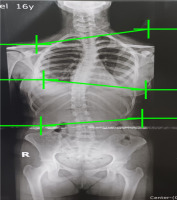

This retrospective cohort study examined 130 medical records of adolescent patients at the Physical Therapy and Rehabilitation Centre, South Valley University, Egypt, between May 2021 and October 2022. Patient clinical and demographic data were extracted from medical records, including age, gender, height, weight, serum vitamin D level, and Cobb angle. The inclusion criteria were patients diagnosed with scoliosis (Cobb angle ≥ 10°), and the exclusion criteria were patients with a history of walking difficulties, including congenital postural abnormalities, lower limb discrepancy, congenital anomalies, hemivertebrae, muscular dystrophy, and spina bifida. Scoliosis was identified when the Cobb angle was ≥ 10°, which was calculated by measuring the largest spinal curve, taken from the upper-end vertebra to the lower-end vertebra, using X-ray records. An experienced radiologist was responsible for measuring and reporting the Cobb angle. Patients had a choice of morning, afternoon, or evening sessions for laboratory measurements. Fasting was required for 12 hours before the morning examination or six hours before the afternoon or evening examination. Vitamin D levels [25-hydroxyvitamin D (25 (OH) D] were determined from frozen serum samples using electrochemiluminescence immunoassays (Roche, IN, USA). According to the American Academy of Paediatrics, vitamin D is deficient when < 20 ng/ml and sufficient if > 20 ng/ml [35]. Figure 1 shows a sample of the Cobb angle measurement of a 13-year-old boy.